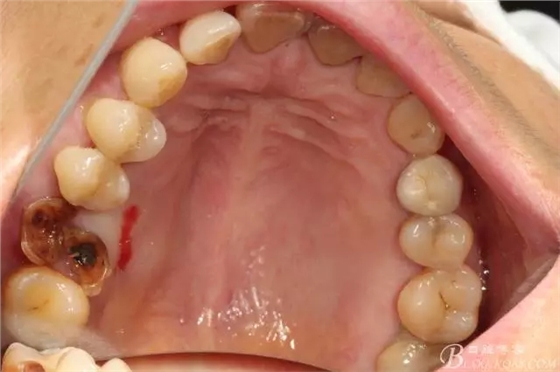

左上后牙巨大拔牙窩即刻種植+右下前磨牙簡(jiǎn)單即刻種植一例

病人右下前磨牙突然折斷 要求種牙 ,當(dāng)然即刻種植是我的強(qiáng)項(xiàng)嘛,那就先牙周治療然后約時(shí)間吧?;颊咭笞笊虾笱酪矌нM(jìn)(帶帶進(jìn)的意思就是一起種種掉)

先26號(hào)牙位拔牙前照片顯示牙根頰舌向已經(jīng)裂開(kāi)